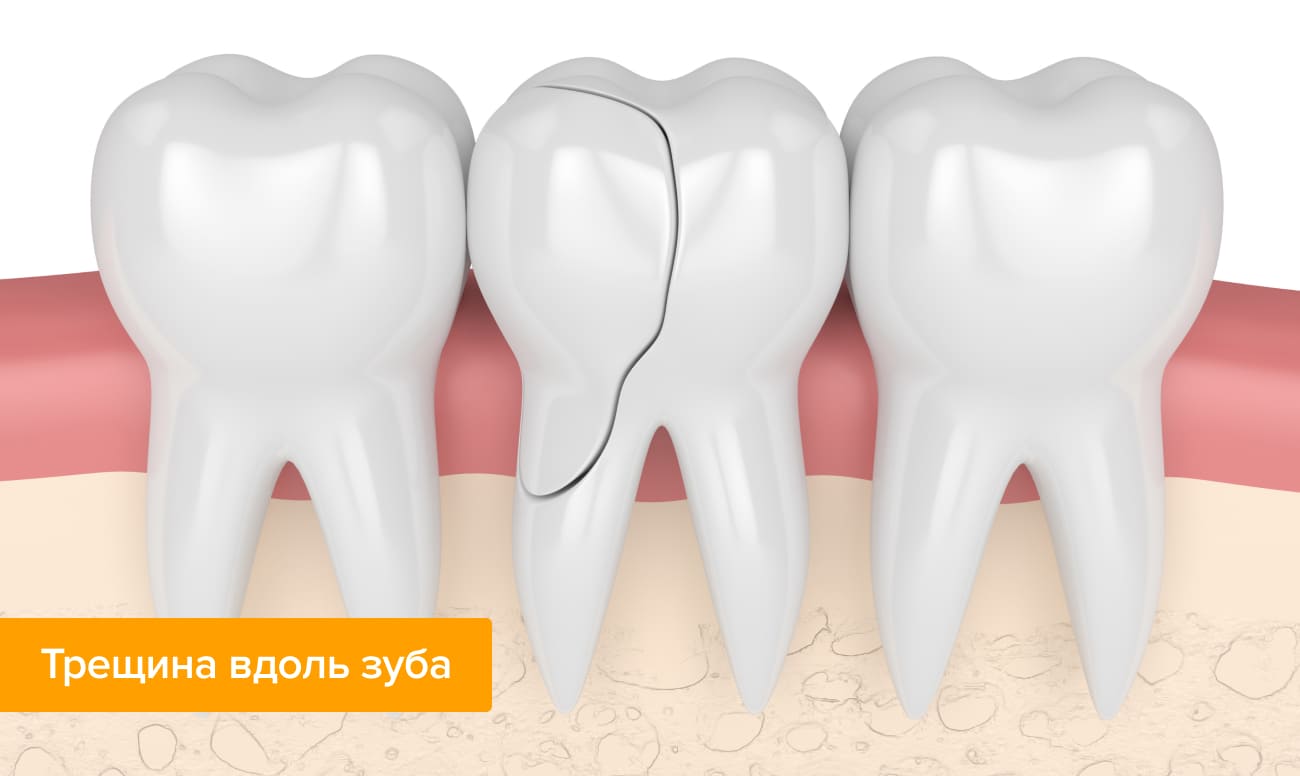

Вертикальные

Вертикальная полоса чаще всего возникает на переднем зубе. Она может идти вдоль всей поверхности, затрагивая корень. Если будет затронута пульпа, то зуб придется удалить. Так что, если вами обнаружена продольная полоса, то следует незамедлительно обратиться к стоматологу, чтобы лечение прошло быстро и безболезненно.

Направление и глубина трещины подскажут врачу, каковы перспективы развития заболевания и насколько срочно требуется лечение. Например, неглубокая трещина вдоль зуба достаточно безопасна и не всегда требует вмешательства, хотя пациенту следует внимательно следить за своим состоянием: если появилась боль, изменился цвет эмали или усилилась чувствительность, лечиться все же придется. А вот горизонтальные и диагональные трещины значительно опаснее: под нагрузкой они очень быстро приводят к разрушению тканей. Скрытые трещины можно увидеть только на рентгеновском снимке, лечить их сложнее всего.

Повреждения могут возникать на любом участке эмали, самое опасное – это раскол корня зуба. Соответственно клинической картине, типу повреждения, стоматолог подбирает терапевтическую схему. Виды трещин и степень их опасности:

Вертикальные. Чаще всего неглубокие, и не вызывают никакого физического дискомфорта. Если не нагружать зуб и не злоупотреблять сменой горячего-холодного, то к серьёзным последствиям не приводят. К врачу показаться, всё же, стоит – чтобы маскировать патологию и предотвратить потемнение её краёв;